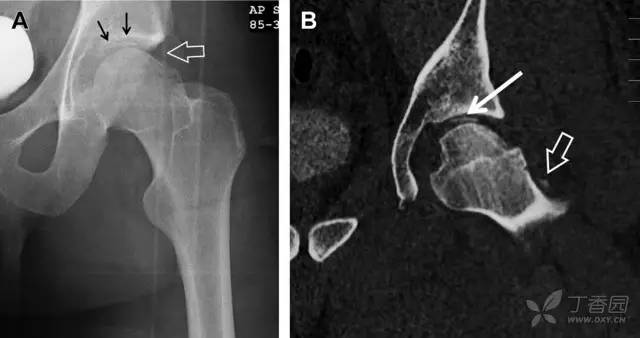

股骨头骨折常与髋关节脱位有关。需要关注的是那些既不是因剪力损伤也不是因直接*力暴**作用造成的骨折。这些类型的骨折可能十分轻微。提倡应用 CT 检查,不仅可诊断骨折,而且能评估关节内骨折碎片的位置(图 6)。

图 6 股骨颈骨折伴髋关节脱位。A 股骨头上外侧轮廓缺失(空箭头)关注嵌入上方关节间隙的骨折碎片(黑色箭头)B 冠状位 CT 多维重建(MPR)证实骨软骨碎片(白色箭头)和关节上方的另一个碎片(空箭头)